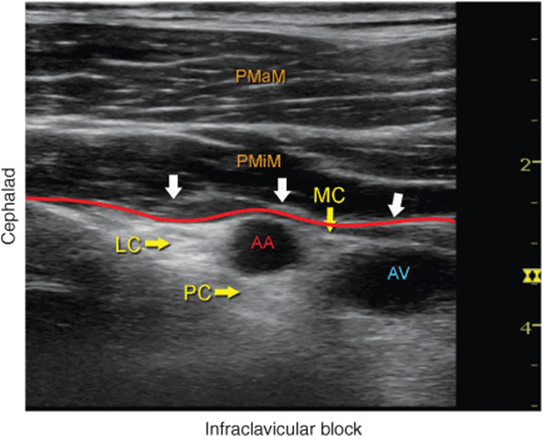

The axillary artery can be identified deep to the pectoralis major and minor muscles. An effort needs to be made to obtain clear views of both pectoralis muscles and their respective fasciae. This is important because the area of interest lies underneath the fascia of the pectoralis minor muscle. Surrounding the artery are the three cords of the brachial plexus: the lateral, posterior, and medial cords. These are named for their usual position relative to the axillary artery, although there is a great deal of anatomic variation. With the left side of the screen corresponding to the cephalad aspect, the cords can often be seen as round hyperechoic structures at approximately 9 o’clock (lateral cord), 7 o’clock (posterior cord), and 5 o’clock (medial cord) (Figures 31-2, 31-3, and 31-4). The axillary vein is seen as a compressible hypoechoic structure that lies inferior, or slightly superficial, to the axillary artery. Multiple other, smaller vessels (e.g., the cephalic vein) are often present as well. The transducer is moved in the superior-inferior direction until the artery is identified in cross-section. Depending on the depth of field selected and the level at which the scanning is performed, the chest wall and lung may be seen in the inferior aspect of the image. The axillary artery and/or brachial plexus are typically identified at a depth of 3 to 5 cm in average size patients.

FIGURE 31-4. Labeled ultrasound image of the brachial plexus (BP) in the infraclavicular fossa. LC, lateral cord; PC, posterior cord; MC, medial cord. Note that the brachial plexus and the axillary artery (AA) are located below the fascia (red line) of the pectoralis minor muscle (PMiM). PMaM, pectoralis major muscle.